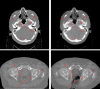

Purpose: The incorporation of cone-beam computed tomography (CBCT) has allowed for enhanced image-guided radiation therapy. While CBCT allows for daily 3D imaging, images suffer from severe artifacts, limiting the clinical potential of CBCT. In this work, a deep learning-based method for generating high quality corrected CBCT (CCBCT) images is proposed.

Methods: The proposed method integrates a residual block concept into a cycle-consistent adversarial network (cycle-GAN) framework, called res-cycle GAN, to learn a mapping between CBCT images and paired planning CT images. Compared with a GAN, a cycle-GAN includes an inverse transformation from CBCT to CT images, which constrains the model by forcing calculation of both a CCBCT and a synthetic CBCT. A fully convolution neural network with residual blocks is used in the generator to enable end-to-end CBCT-to-CT transformations. The proposed algorithm was evaluated using 24 sets of patient data in the brain and 20 sets of patient data in the pelvis. The mean absolute error (MAE), peak signal-to-noise ratio (PSNR), normalized cross-correlation (NCC) indices, and spatial non-uniformity (SNU) were used to quantify the correction accuracy of the proposed algorithm. The proposed method is compared to both a conventional scatter correction and another machine learning-based CBCT correction method.

Results: Overall, the MAE, PSNR, NCC, and SNU were 13.0 HU, 37.5 dB, 0.99, and 0.05 in the brain, 16.1 HU, 30.7 dB, 0.98, and 0.09 in the pelvis for the proposed method, improvements of 45%, 16%, 1%, and 93% in the brain, and 71%, 38%, 2%, and 65% in the pelvis, over the CBCT image. The proposed method showed superior image quality as compared to the scatter correction method, reducing noise and artifact severity. The proposed method produced images with less noise and artifacts than the comparison machine learning-based method.